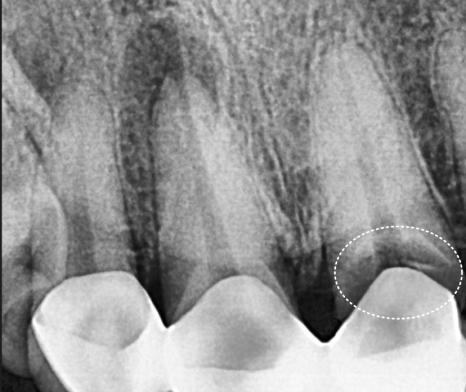

방사선 상, 보철 경계 부위가

까맣게 나타나는 것을 보아

아무래도 2차 충치의 가능성이 높아

브릿지를 제거해보기로 했습니다.